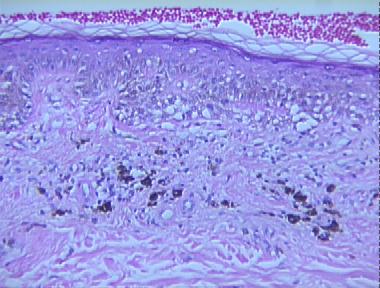

regressed melanoma

Histologic Features